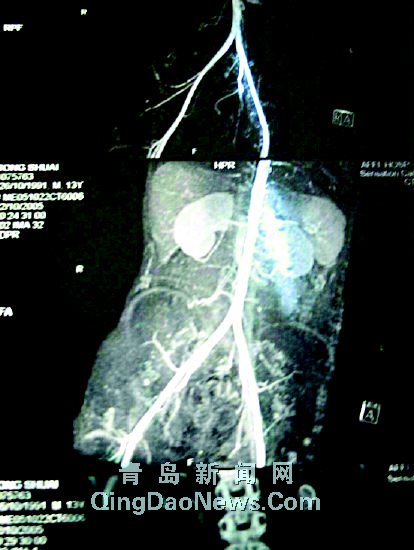

| 從小可的CT片可以明顯看出長了4個腎。格寧為鵬攝 |

CT片顯示4個腎

在青醫(yī)附院小兒外科,記者見到了小可的一張CT片。在楊主任的介紹下,記者在上面清楚地看出小可的腎臟情況,一邊明顯有兩個腎臟,一邊不明顯,但也是由兩個腎重疊而成。楊主任認為,雖說這也是一種畸形現(xiàn)象,好在它們的基本功能比較正常。除此之外,小可的病情與最初通過外觀診斷的相差無幾,主要是膀胱外翻、尿道閉鎖和膀胱直腸漏。